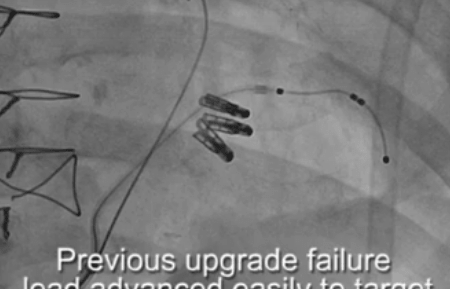

Case previous implant failure over the wire LV lead removal, subclavian venoplasty Vein selector LVI